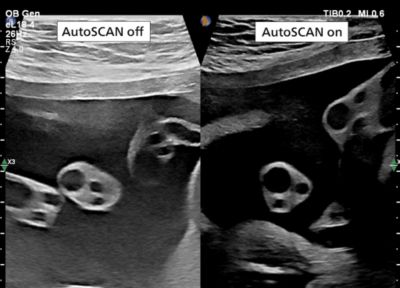

eL18-4 transducer image showing visual difference of scan with and without utilizing of autoSCAN

Enhance workflow with real-time image adjustments with AutoSCAN

AutoSCAN enhances workflow by automatically and continuously making real-time adjustments to achieve balanced brightness of tissues. By dynamically adjusting every pixel on every scan line, each image frame has individually adjusted image brightness on 2D, 3D and M-mode.